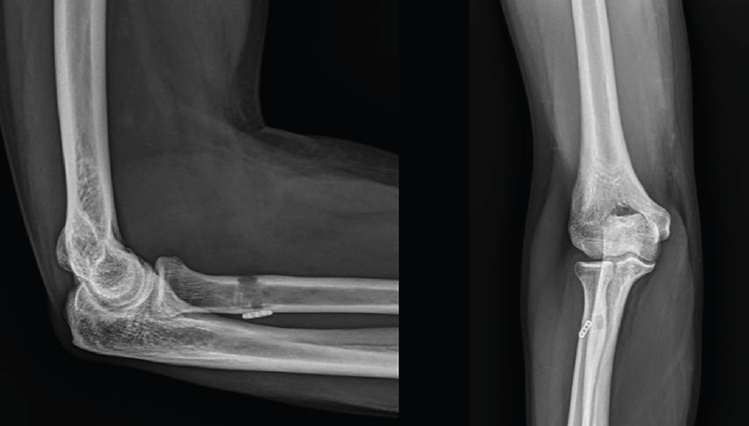

La técnica quirúrgica empleada para el tratamiento de estas roturas consiste en la reinserción del tendón avulsionado en la tuberosidad bicipital del radio, pero a pesar de que todas las modalidades han sido extensamente estudiadas, sigue habiendo controversia al respecto. Las variantes son reinserción “anatómica” o “no anatómica”, abordaje a través de “2 incisiones” o “incisión anterior única” y los diferentes sistemas de fijación(35). En las reparaciones mediante incisión única (Figura 6), tanto la preparación del tendón como la reinserción se hace a través de una incisión longitudinal o transversa en la fosa antecubital aprovechando el canal tendinoso original. En la técnica de doble incisión, se realiza la recuperación y preparación del cabo tendinoso a través de una incisión limitada anterior y la reinserción en la tuberosidad se realiza a través de un segundo abordaje, en este caso posterior, sin exponer el cúbito para evitar la aparición de osificaciones heterotópicas dolorosas que pueden limitar la pronación y supinación del antebrazo. Normalmente, la reinserción a través de una incisión se realiza mediante fijación a la 2.ª cortical con un dispositivo de tipo “botón” (Figura 7), aunque también se ha descrito con implantes directos y con tornillos de biotenodesis, mientras que, si se opta por la reparación a través de doble incisión, la reinserción se suele realizar a través de túneles óseos. Debido a la íntima relación entre abordaje y sistema de fijación, es difícil establecer los riesgos y los beneficios de las distintas variantes de forma individual y todavía no existe consenso sobre el mejor método de reparación. De acuerdo con la bibliografía disponible y a pesar de que el abordaje mediante doble incisión parece reproducir mejor la inserción anatómica del tendón(36), se puede afirmar que, con pequeñas diferencias, la mayoría de las técnicas disponibles pueden ofrecer buenos resultados funcionales en la gran mayoría de los pacientes(35,37,38), siendo clave la posibilidad de la movilización temprana y evitar posibles complicaciones. En relación con estas últimas, no es desdeñable el porcentaje reflejado en la bibliografía, entre el 20 y el 25%. Las más frecuentes son la osificación heterotópica y la rigidez en el abordaje por doble incisión, y la neuroapraxia del nervio antebraquial cutáneo externo en el abordaje por incisión mínima, siendo los túneles óseos y el botón cortical los sistemas de fijación con menor tasa de complicación(39).

Figura 7. Reinserción del tendón distal con dispositivo de tipo botón cortical. Obsérvese el distinto diámetro del túnel en primera y segunda cortical.